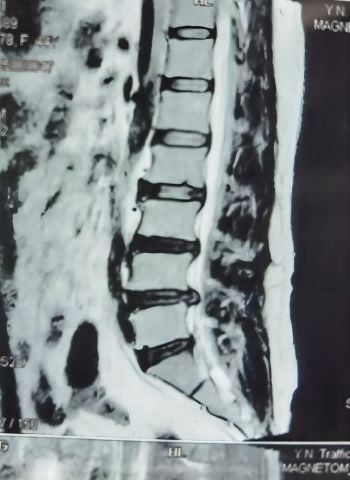

术前MR

患者因腰椎间盘突出引起右侧腰腿痛伴右下肢麻木、不能站立行走、卧床翻身困难一周入院,行CT及MR检查确诊为腰椎间盘突出伴神经根压迫,在局部麻醉下行椎间孔镜微创手术,术后第二天腰腿痛及麻木缓解,能下床行走,5天后治愈出院。